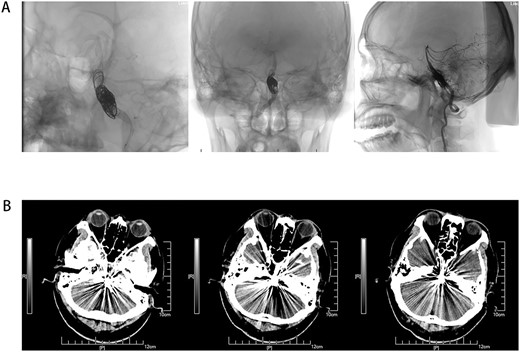

Male, AA, 44 years old, admitted in July 2022 with recurrent pain on the left side of the maxillofacial region for ~1 year. In the last 6 months, the dose of carbamazepine was increased to 300 mg three times daily, but the control of facial pain was still unsatisfactory, so the patient and his family numbers requested to be hospitalized for surgery. The patient had a history of hypertension for ~15 years. The maximum blood pressure was ~200/120 mmHg. The nifedipine controlled-release tablet was used to control his blood pressure by 30 mg daily, which is maintained at ~140/80 mmHg. The neurological examination on admission was unremarkable. TN was assessed as grade V according to the Bar row Neurological Institute classification. Magnetic Resonance Imaging (MRI) of the head suggests small ischemic focus in the pons and cerebellum; marked extending of the basilar artery (Fig. 1A–C). To clarify the etiology, doppler ultrasound of the carotid and vertebral arteries bilaterally revealed no atheromatous plaque or hemodynamics abnormalities. An electrocardiogram and cardiac function and cardiac ultrasound were performed. The results were normal. Biochemical tests for blood cell count, liver function, kidney function, and glucose test revealed no abnormalities. The Digital subtraction angiography (DSA) was given to the patient (Fig. 2A and B). Antiplatelet aggregation therapy with a combination of clopidogrel and aspirin was used before operation. The DSA displayed the VBD, the VBD was length 2.5 cm and width 9 mm, its path was tortuous and deviated to the left. Normal blood flow in the middle venous phase of the imaging was normal. Stent-assisted interventional embolization was chosen. A suitable coil was selected to form basket by EV3 (20 mm*50 cm, Medtronic, USA) and the stent catheter was withdrawn and repositioned through the coil into the right posterior cerebral artery. Release stent 1: LEO (5.5 mm*60 mm, LEO, USA), then choose the appropriate ring (14 mm*30 cm, 13 mm*30 cm, 12 mm*30 cm, 10 mm*30 cm, Taijie Weiye, China) to occlude the dilated artery (Fig. 3A). Postoperatively, we scanned the Computed Tomography (CT) (Fig. 3A), the TN was completely relieved, but there was residual left-sided facial palsy with a House-Brackmann grade IV and a grade III right limb muscle strength. Systematic treatment was operated at the rehabilitation unit, once the condition was stabilized. At 3 months post-operative follow-up the patient showed significant improvement in muscle strength in the right limb, with muscle strength grade V− and significant improvement in facial palsy, which was graded House-Brackmann grade II.

(A) MRI 3D-TOF(3 digital- time of flight), (B) MRI T2, C:MRI T1. Basilar trunk dilation up to 9 mm of diameter deviated path to the left side responsible of medulla compression.